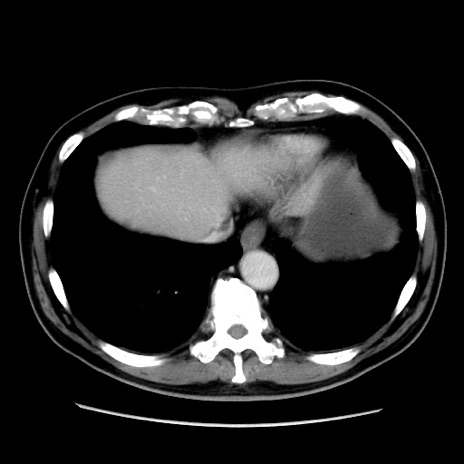

冠状断像

【現病歴】 約1ヶ月前より間欠的に腹痛と嘔吐あり、当院消化器内科を受診したところCTで多発する肝臓のLDAを指摘され、精査中であった。以降は消化器症状は安定していたが、2日前より嘔気と腹痛があり、同日より排便・排ガスが消失した。改善認めず、 本日、救急外来を受診した。